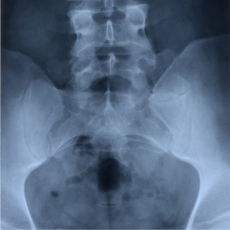

The tailbone is the small bone at the bottom of your backbone, or spine. Tailbone disorders include tailbone injuries, pain, infections, cysts and tumors. You rarely break your tailbone. Instead, most injuries cause bruises or pulled ligaments. A backward fall onto a hard surface, such as slipping on ice, is the most common cause of such injuries. Symptoms of various tailbone disorders include pain in the tailbone area, pain upon sitting, pain or numbness in the arms or legs due to pressure on nerves in the tailbone area, and a mass or growth you can see or feel.